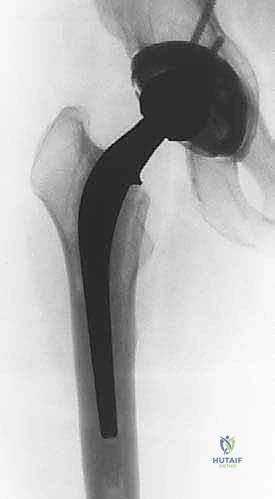

- الأشعة السينية التقليدية (X-rays): صور متعددة الزوايا لتقييم التآكل العظمي، هجرة المكونات، وتحديد تصنيف فقدان العظم (مثل تصنيف Paprosky).

- الأشعة المقطعية (CT Scan): ضرورية للغاية لتقييم مخزون العظم الحُقّي (في الحوض) وتحديد حجم التجاويف العظمية بدقة ثلاثية الأبعاد. تساعد في التخطيط لاستخدام دعامات معدنية أو ترقيع عظمي.

- القوالب الرقمية (Digital Templating): استخدام برامج حاسوبية متقدمة لتراكب صور الغرسات الجديدة على أشعة المريض، لتحديد المقاسات المتوقعة، ومكان مركز الدوران، وطول الساق لتجنب قصر أو طول الطرف بعد الجراحة.

- تحديد استراتيجية الإزالة: بناءً على نوع الغرسة القديمة (أسمنتية أم غير أسمنتية)، يحدد الجراح الأدوات المطلوبة (أزاميل مرنة، مناشير، نظام استخراج الكأس، أدوات الموجات فوق الصوتية لإزالة الأسمنت).